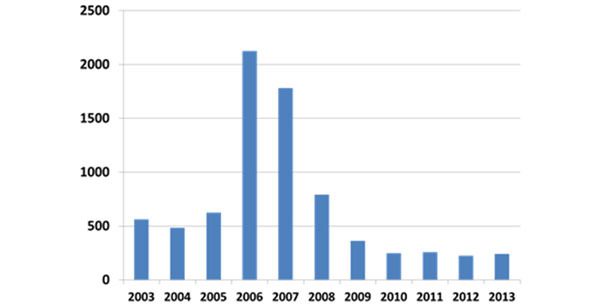

Durante a fase epidémica (2004-2007), as mortes por PCVAD na engorda chegavam aos 40 %, produzindo uma queda na comercialização de quase 10 % nos EUA. Em princípios de 2006, os produtores pediam desesperadamente uma medida efectiva. Pese que vários grupos de investigação estavam a trabalhar no desenvolvimento de uma vacina comercial desde finais dos anos 90, nos EUA não se comercializou nenhuma até 2006 e não esteve completamente disponível até 2007-2008. As vacinas comerciais demonstraram ser consideravelmente eficazes, tanto na prevenção das devastadoras perdas causadas pelas mortes e pela redução do crescimento como no aumento do rendimento global e na diminuição da variabilidade no ganho de peso. A aplicação com êxito das vacinas comerciais para prevenir as perdas por morte têm continuado até à data. Na figura 2 mostra-se a evolução do número de diagnósticos no laboratório de veterinária da Universidade do Iowa (ISU VDL).

Figura 2: Frequência relativa do diagnóstico de PCVAD (ISU VDL)

As vacinas continuam a ser eficazes contra a PCVAD e quase todos os animais produzidos comercialmente nos EUA estão vacinados mas, devido a que o PCV2 continua a circular nas populações vacinadas, nalguns casos continuam a aparecer casos de PCVAD.